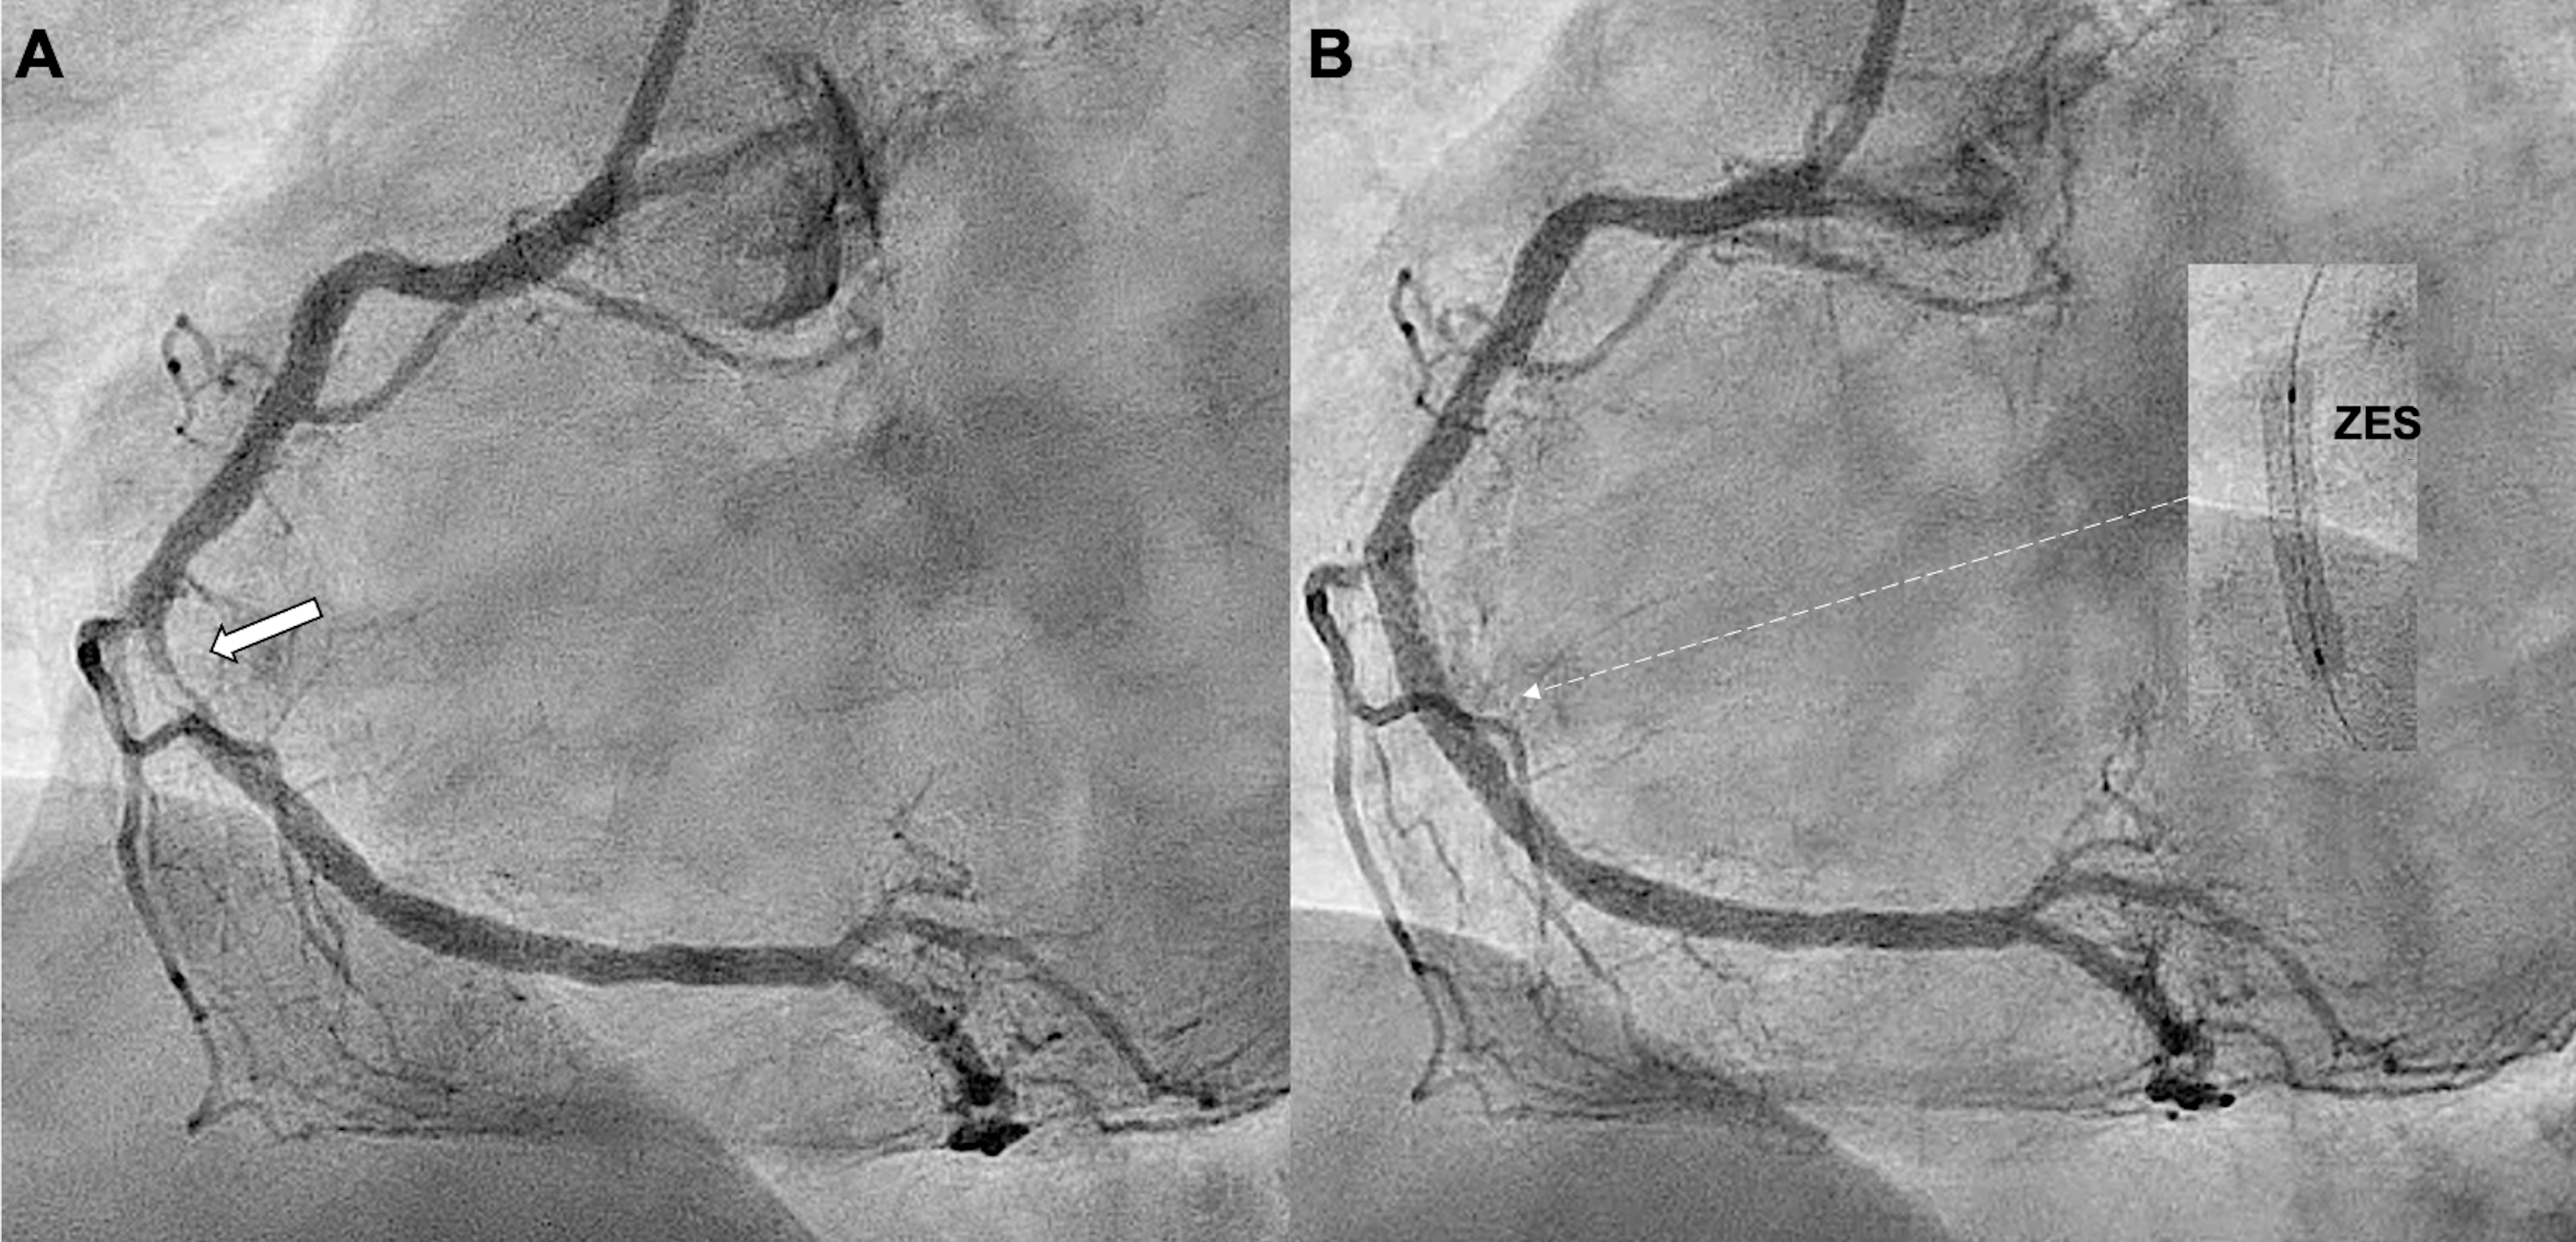

Two hours later, the patient developed recurrent chest pain with inferior ST-segment re-elevation. Repeat CAG revealed acute stent thrombosis (AST) (Figure 2A, Video 2). Thrombus aspiration was performed, and intravascular ultrasound (IVUS) showed a large diffuse intramural hematoma (IH) distal to the ZES, without underexpansion or malapposition (Figure 2B). The IH was fenestrated using a 3.5 x 6.0-mm cutting balloon (Figure 3A, Video 3). Repeat IVUS confirmed multiple fenestration tracts (Figure 3B, Video 4). Two additional overlapping ZES were successfully implanted (Figure 3C). The patient was discharged uneventfully after 48 hours and remained asymptomatic at the 1-month follow-up.